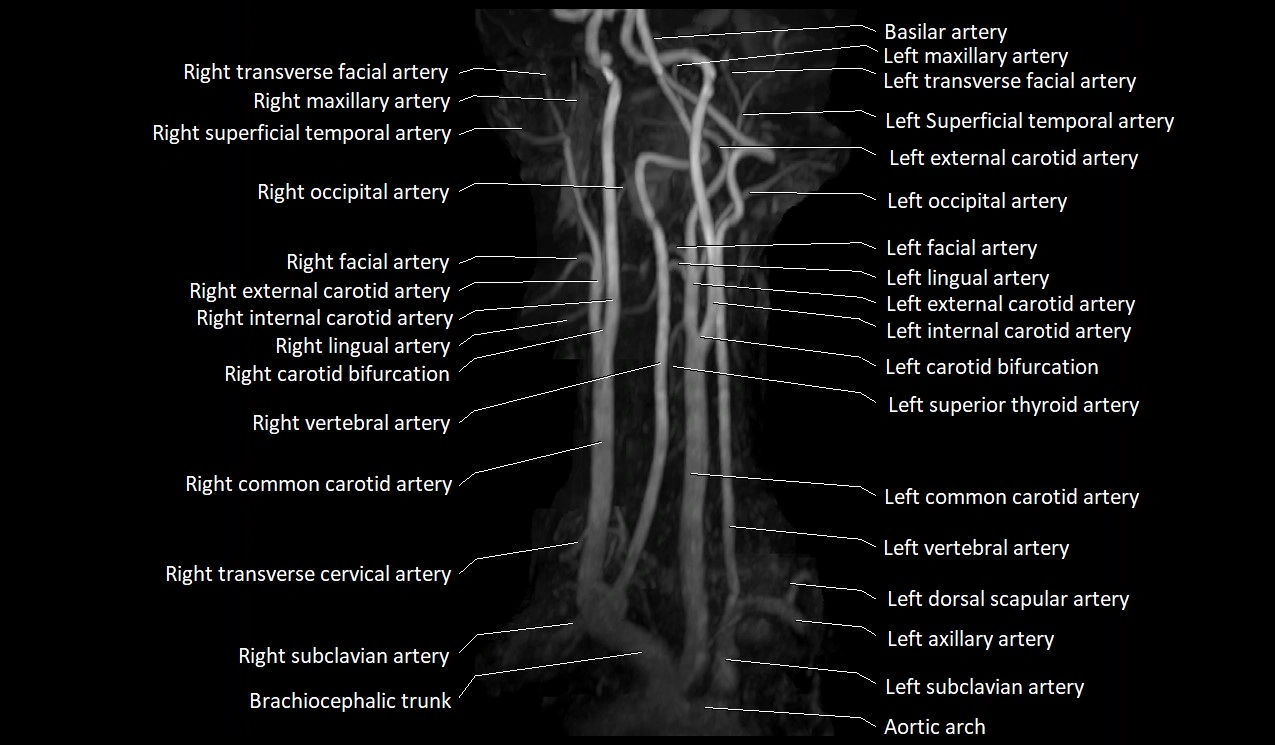

MRI images

image